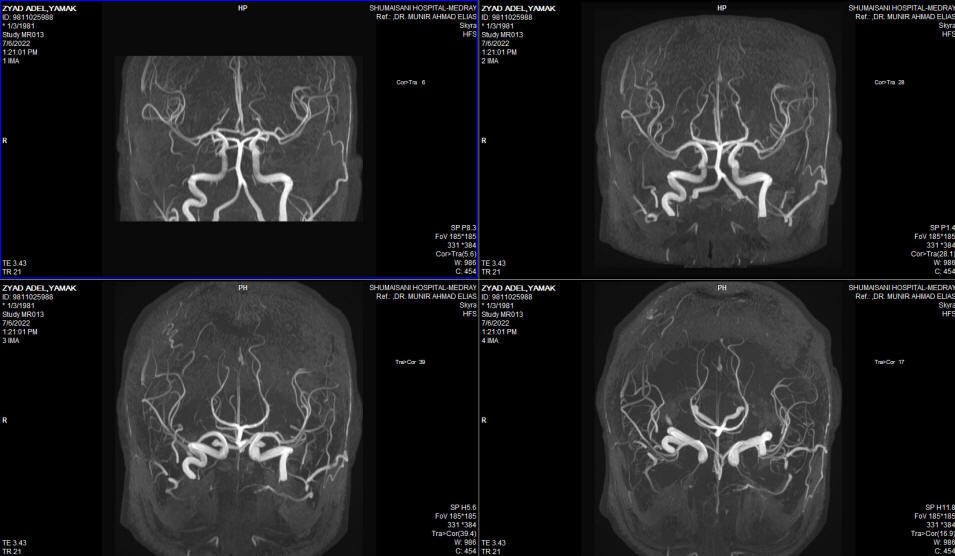

The patient then came 26-June-2002 complaining of double vision, complete hearing loss left side, but he walk without aid with almost complete recover of the left facial nerve. Still complaining of swallowing difficulty, but he mention that the assort of the eating food is widening, but still using PEG.  MRI of the brain done 06-July-2022 showing massive malacia of the left cerebellar hemisphere. The brain stem and the posterior circulation are intact. The MRV showing absent left transverse sinus , which could be a variant. The left trigeminal nerve is not compressed and the canal is wide.

Fig:-5 MRV showing absence of left transverse sinus which could be a normal variant.